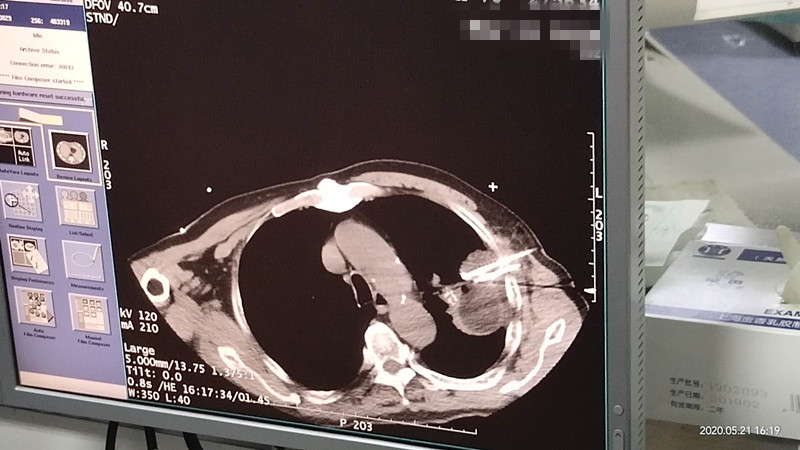

76岁肺部氩氦刀冷冻消融